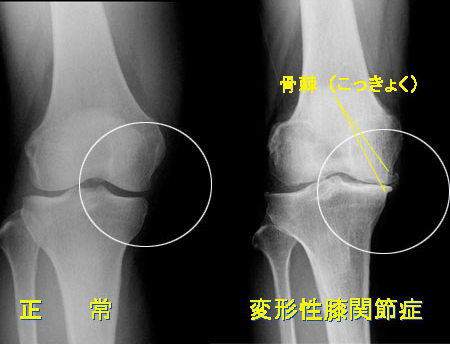

手術になる関節とは